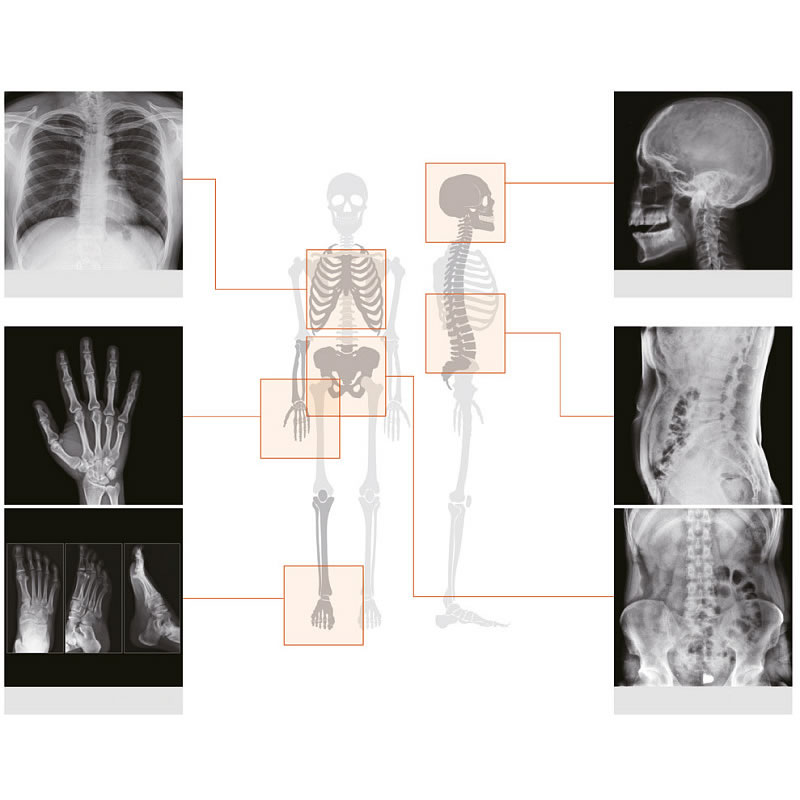

SET CAMERA A RAGGI X REMEX KA6: camera (32000) + rilevatore + laptop con software Camera a raggi X portatile utilizzabile per adulti e bambini per consentire a personale qualificato e addestrato di produrre immagini diagnostiche a raggi X dell’intero corpo. Qualità superiorie delle immagini, esposizione bassa alle radiazioni, sempre e ovunque. L’accesso rapido ne consente l’impiego quando non è sicuro o pratico spostare un paziente dal letto o quando l’immagine a raggi X è richiesta con urgenza. Connettività wireless integrata. Copertura estesa dei dati clinici Acquisizione di tutte le parti del corpo umano, inclusi torace, area pelvica, addome, mani e testa dei pazienti adulti. Impostazione in meno di 1 minuto. Esposizione minima alle radiazioni Il design e l’apposito meccanismo di limitazione riducono al minimo l’esposizione alle radiazioni. Immagini acquisite in meno di 3 secondi. Collimatore brevettato ad aree attive regolabili Il collimatore brevettato riduce le perdite e le radiazioni diffuse. Immagini raggi X di qualità superiore – 70 kV: penetrazione immagine potenziata per identificare meglio le ossa – 6 mA: tempo ridotto di irradiazione per ridurre sfocatura da movimento – macchia focale 0,4 mm per risoluzione elevata Funzione Beam guidata da LED e laser Per identificare area di esposizione accurata. CAMPI DI APPLICAZIONE: Pronto soccorso Checkup medico Case di riposo UTIN (Unità Terapia Intensiva Neonatale) UTI (Unità Terapia Intensiva) Ortopedia Medicina respiratoria Sala operatoria Stanza di Isolamento a Pressione Negativa